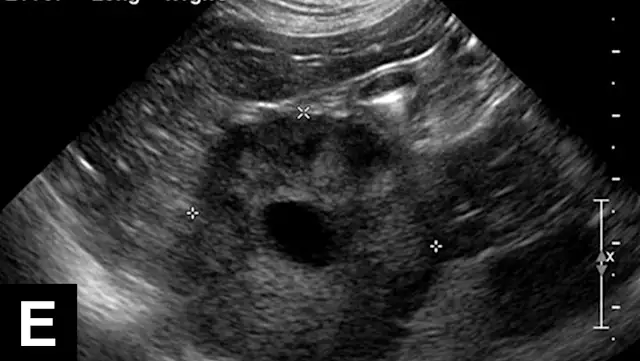

Figure 3A

Focal hepatic lesions demonstrating multiple appearances on ultrasound: Hypoechoic nodule representing nodular regeneration in a dog (A). Hyperechoic nodule representing metastatic carcinoma in a dog (B). Cavitated hyperechoic nodule representing benign cystadenoma in a cat (C). Mixed-echogenic nodule with target-like appearance representing metastatic sarcoma in a dog (D). Mixed-echogenic, cavitated hepatic mass representing hepatocellular carcinoma in a dog (E).Large hypoechoic mass representing histiocytic sarcoma in a dog (F). Two anechoic nodules representing benign hepatic cysts in a dog (G).